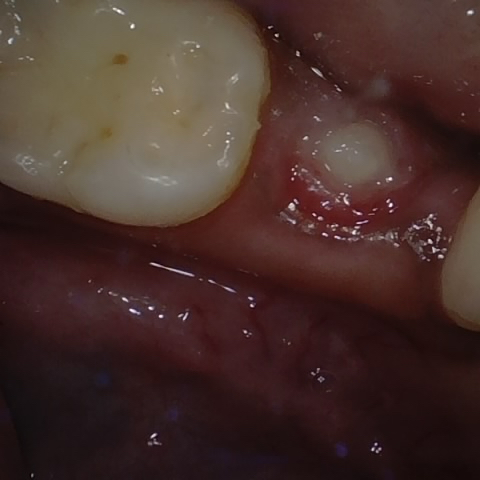

Annotated as "Good"